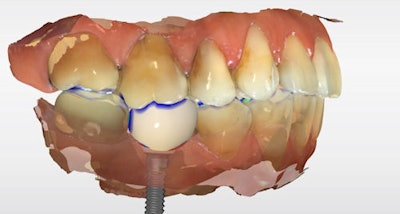

The definitive crown was then designed in CEREC software (Figure 4) using virtual articulation and occlusal analysis (Figure 5) and verified in a full-arch digital view for occlusal harmony (Figure 6). Milling was completed using CEREC Primemill with a Katana Zirconia One for Implant block, producing excellent marginal adaptation and lifelike translucency (Figure 7).

Figure 4: Digital crown design in CEREC software.

Figure 5: Virtual articulation and occlusal analysis.

Figure 6: Full-arch digital verification.